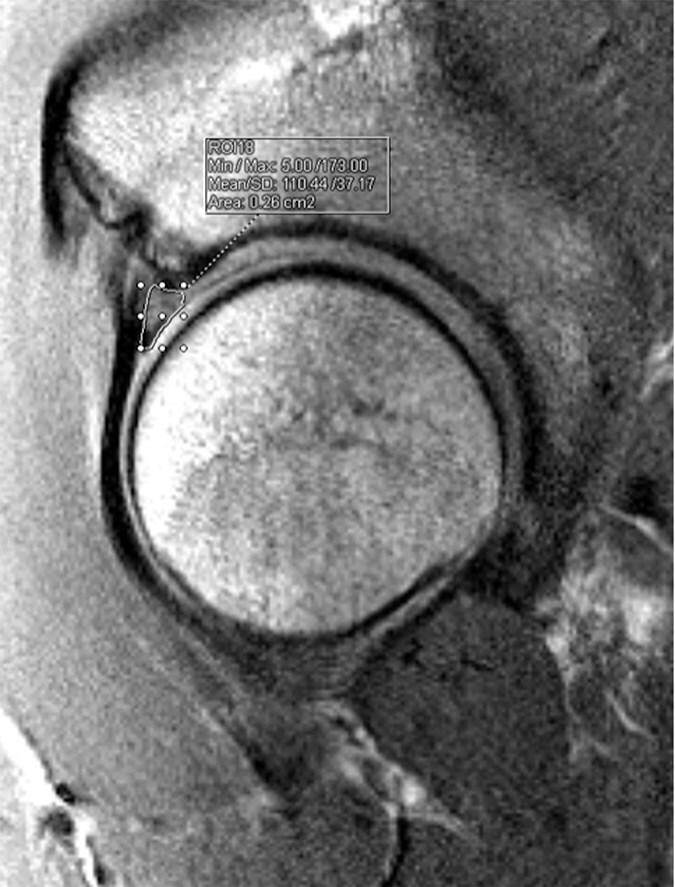

术前x线测量可以帮助预测髋关节唇裂患者最终接受修复还是初级重建。本研究调查了影像学参数是否:(i)术前预测唇部修复与重建,(ii)与唇部T2磁共振成像(MRI)定位值相关。这项回顾性比较研究包括14-50岁的患者,他们在一个机构接受了2年以上的唇部修复或重建。既往有开放或关节镜髋关节手术或术前CT和MRI成像不充分的患者被排除在外。在术前MRI图像的多个位置测量唇部大小。盲法评价者采用三维CT分析记录外侧中心边缘角(LCEA)、髋臼版本、Tonnis角、髋臼覆盖、α角、股扭转和颈轴角(FNSA)。通过对每位患者的最佳矢状切面进行测序分析,获得唇部的T2 MRI定位值。单变量混合线性模型用于确定每次x线摄影测量与决定修复或重建阴唇之间的关联。包括52例手术。唇部大小对进行唇部重建和修复没有预测作用。接受唇部重建的可能性与LCEA (P = 0.003)和Tonnis角(P = 0.034)相关。(P

Preoperative radiographic measurements may help predict which patients with hip labral tears ultimately undergo repair versus primary reconstruction. This study investigated if radiographic parameters: (i) preoperatively predict labral repair versus reconstruction and (ii) correlate with T2 magnetic resonance imaging (MRI) mapping values of the labrum. This retrospective comparative study included patients aged 14-50 years who underwent labral repair or reconstruction at a single institution over a 2-year period. Patients with prior open or arthroscopic hip surgery or who had inadequate preoperative computed tomography (CT) and MRI imaging were excluded. Labral size was measured at multiple positions on preoperative MRI images. A blinded reviewer used three-dimensional CT analysis to record lateral center edge angle (LCEA), acetabular version, Tonnis angle, acetabular coverage, alpha angle, femoral torsion, and neck-shaft angle (FNSA). T2 MRI mapping values of the labrum were obtained via sequencing analyses on each patient's optimal sagittal cut. Univariate mixed linear models were used to identify associations between each radiographic measurement and decision to repair or reconstruct the labrum. Fifty-two operations were included. Labral size had no predictive effect on undergoing labral reconstruction versus repair. Likelihood for undergoing labral reconstruction was associated with LCEA (P = .003) and Tonnis angle (P = .034). There was an association (P < .05) between labral T2 mapping values and all radiographic parameters except for FNSA and combined version. Labral size was not associated with whether patients underwent labral reconstruction or repair. The data showed an association between labrum T2 mapping values and nearly all radiographic parameters.